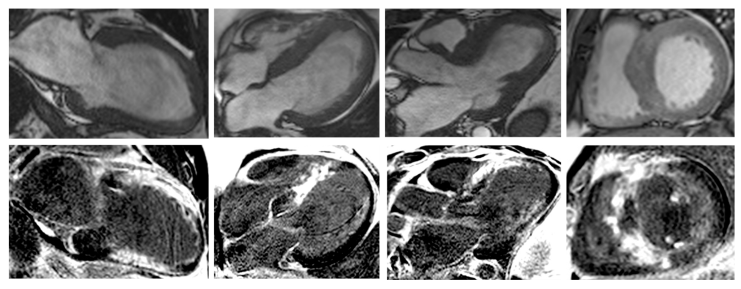

Withal, a recently published study which aimed to compare the effects of CRT in patients with end-stage/dilated HCM by comparing them to patients with dilated cardiomyopathy and ischemic heart disease, pursued the occurrence of LV end-systolic volume decrease at 6-months follow-up. The study concluded that over half of patients with end-stage/dilated HCM were responders to CRT, with improved NYHA class, LVEF and LV end-systolic volume, while QRS duration narrowed from 158.7 ± 32.2 ms to 141.7 ± 22.0 ms, although they had a lower positive response rate to CRT than others (56.3% vs. 69.2% vs. 73.6%) [67]. Likewise, Nakajima et al. compared the impact of CRT on 22 patients with end-stage/dilated HCM and 71 with dilated cardiomyopathy. They have shown that in both groups, CRT significantly relieved symptoms; however, the effects on increasing LVEF and reducing LV end-systolic volume were lower than in those with dilated cardiomyopathy. Moreover, CRT was associated with similar survival and HF hospitalization at 2-year follow-up in both groups, but afterwards, the end-stage/dilated HCM group had significant disease progression and increased mortality [68]. Conversely, in a small study conducted on patients with end-stage/dilated HCM, Killu et al. have shown that in this category of subjects, CRT has rather debatable consequences. Initially, although CRT increased their LV systolic function, in the long term it did not persist, being similar to those without biventricular pacing. Also, they reported no beneficial effect on disease progression [69]. These contradictory results might be argued by variable “molecular responses” and further advanced tissue characterization before CRT might be useful in patients with HCM. Nonetheless, an algorithm regarding cardiac resynchronization in primary prevention of SCD in patients with HCM is presented in Figure 6.

Figure 6. CRT in primary prevention of SCD in patients with hypertrophic cardiomyopathy. * > 140 ms in men and >130 ms in women. Abbreviations: CMR, cardiac magnetic resonance imaging; CRT-D, cardiac resynchronization therapy with defibrillator; CRT-P, cardiac resynchronization therapy with pacemaker; HCM, hypertrophic cardiomyopathy; LV, left ventricle; LVH, left ventricle hypertrophy; NSVT, non-sustained ventricular tachycardia; SCD, sudden cardiac death.